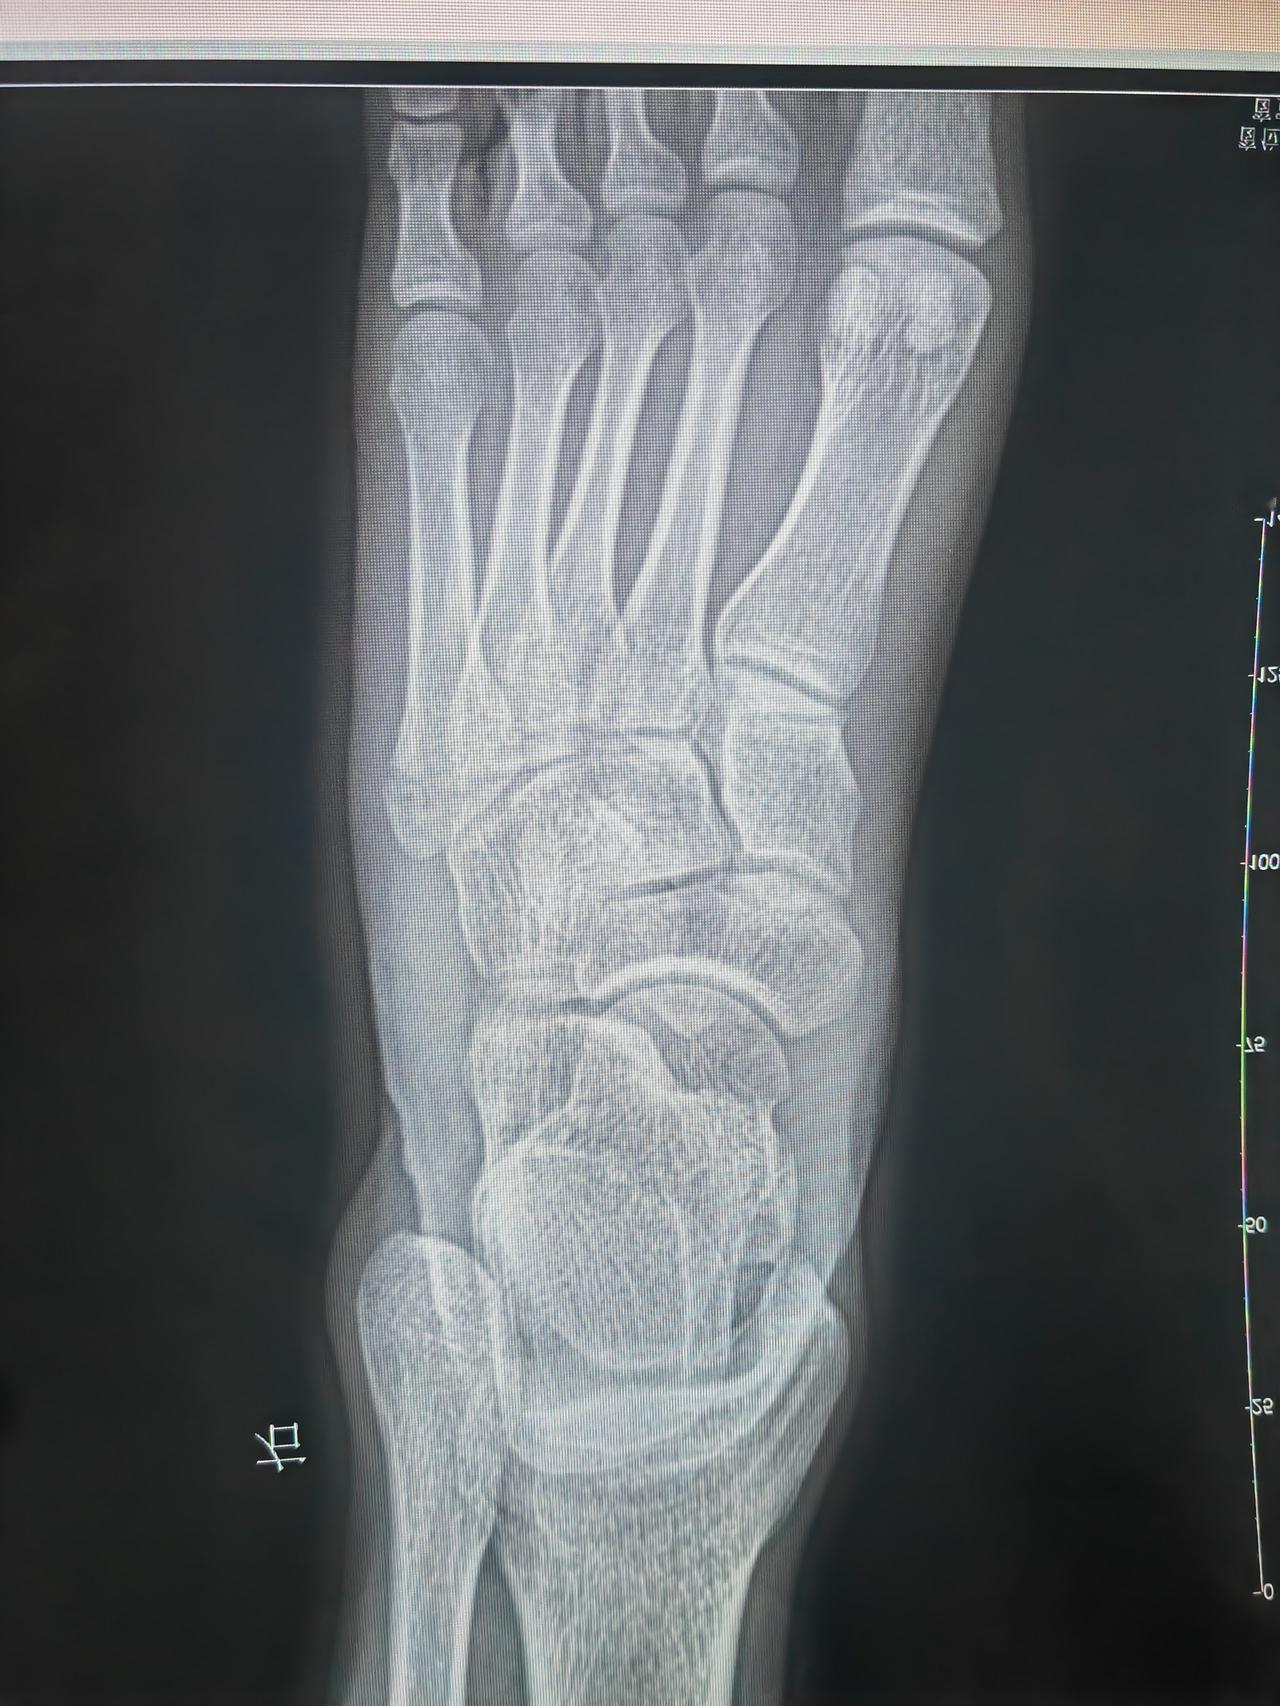

终于拆了,一个月了,小小骨折境限制我自由!伤筋动骨一百天,让它自然慢慢恢复吧